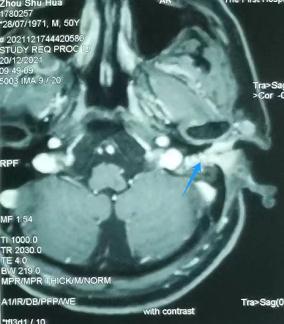

颞骨MRI:左外耳道肿物(蓝色为肿瘤)

张宏征表示,外耳道癌的确诊要靠病理,同时还需要进行听力学、颞骨CT、颞骨颈部增强MRI、肺部CT、超声、ECT等相关检查,肿瘤累及大血管时还需做MRA、MRV,PET-CT可以帮助判断是否出现远处转移。